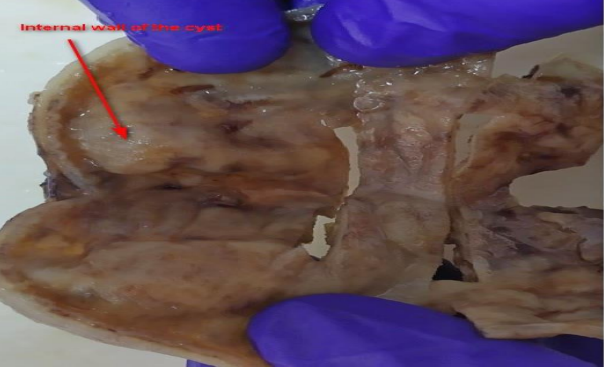

Figure 1: CT-Scan Coronal and Axial planes of the abdominal cavity

A 2815g 5-day-old male patient was born at 37.5 weeks gestation with an APGAR score of 9-10-10. An ultrasound scan identified an intra-abdominal lesion, suggesting a megacolon diagnosis. After birth, further investigations revealed a large extrahepatic unilocular fluid-filled structure measuring 80x30 mm, indicating a mesenteric cyst, cystic lymphangioma, or composite hepatic hamartoma. A cystic mass attached to the terminal ileum was noted at laparotomy, and the cyst and intestine were closely related. The ileon-cyst complex was resected, and end-to-end interrupted primary anastomosis using vicryl 4/0 was performed. The gross pathological specimen showed a 75x10 mm intestinal fragment with ileal mucosa of normal appearance joined to a 80x35cm cystic structure containing mucus without luminal communication. The cyst contained mucus covered by glandular epithelial tissue and shared musculature with the intestinal portion, covered by gastric tissue. The cystic structure shared musculature with the intestinal portion, covered by gastric tissue within normal histological limits. According to the Long classification, the specimen was classified as Type 1B intestinal duplication. The patient's post-operative period was uneventful; at six months, he is thriving well without any complications.

Diagnosis of intestinal duplications is made using chest X-rays, ultrasonography (USG), CT computerized axial tomography, contrasted studies, and diagnostic laparoscopic techniques. In the prenatal period, antenatal ultrasound scans and magnetic resonance imaging can be used for diagnosis. Contrast radiological studies can also be used for differential diagnosis of mesenteric cysts, especially the cystic type. Histological examination is the definitive diagnosis.